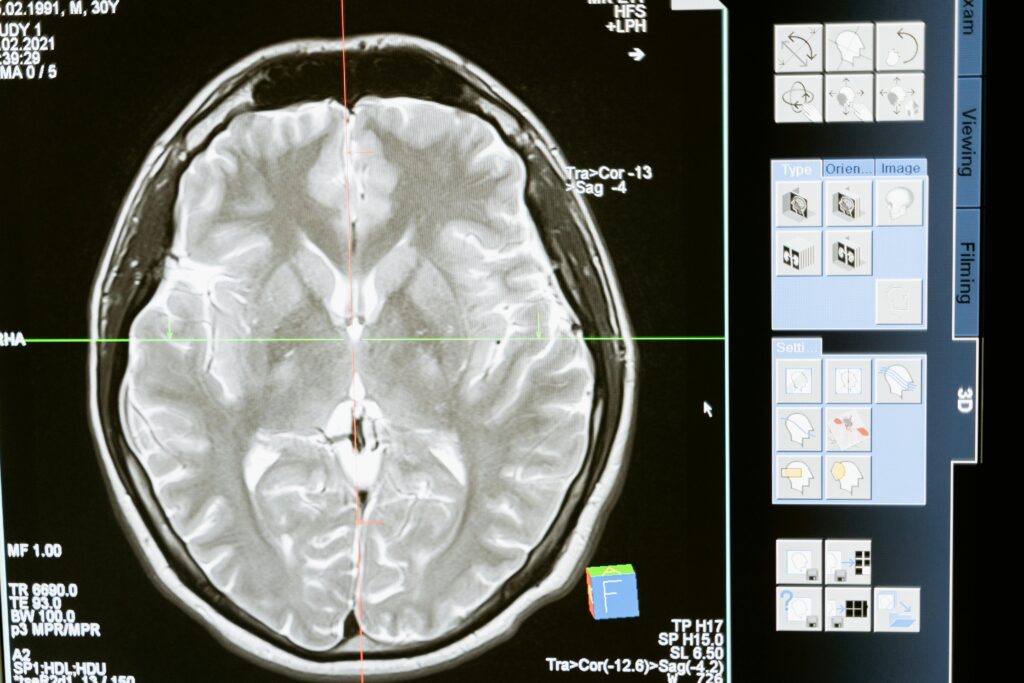

Specialists manage a wide spectrum of conditions, from mild concussions to severe traumatic brain injuries (TBI), which occur when an external force causes damage to the brain. Diagnostic tools are used to determine the extent of injury and guide treatment:

- Imaging studies (such as CT scans or MRIs)